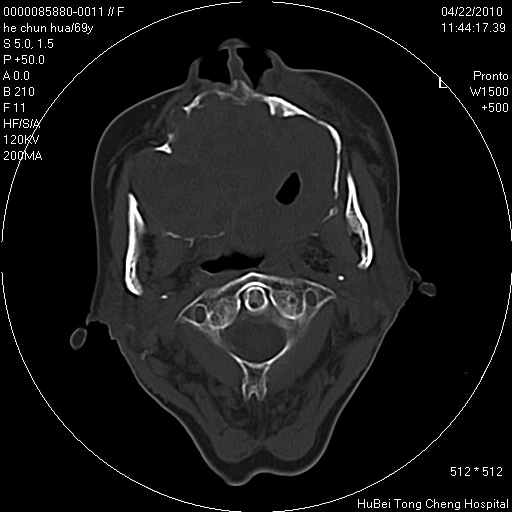

标题: CT25937:女,69Y

硬腭部包块十余年,渐进性增大。

骨源性肿瘤 造秞细胞瘤

还是考虑良性病变,炎症性肌纤维母细胞性肿瘤。

鉴别神经源性肿瘤。

考虑硬腭部肿瘤恶变,gcrg可能,鉴别于gct。